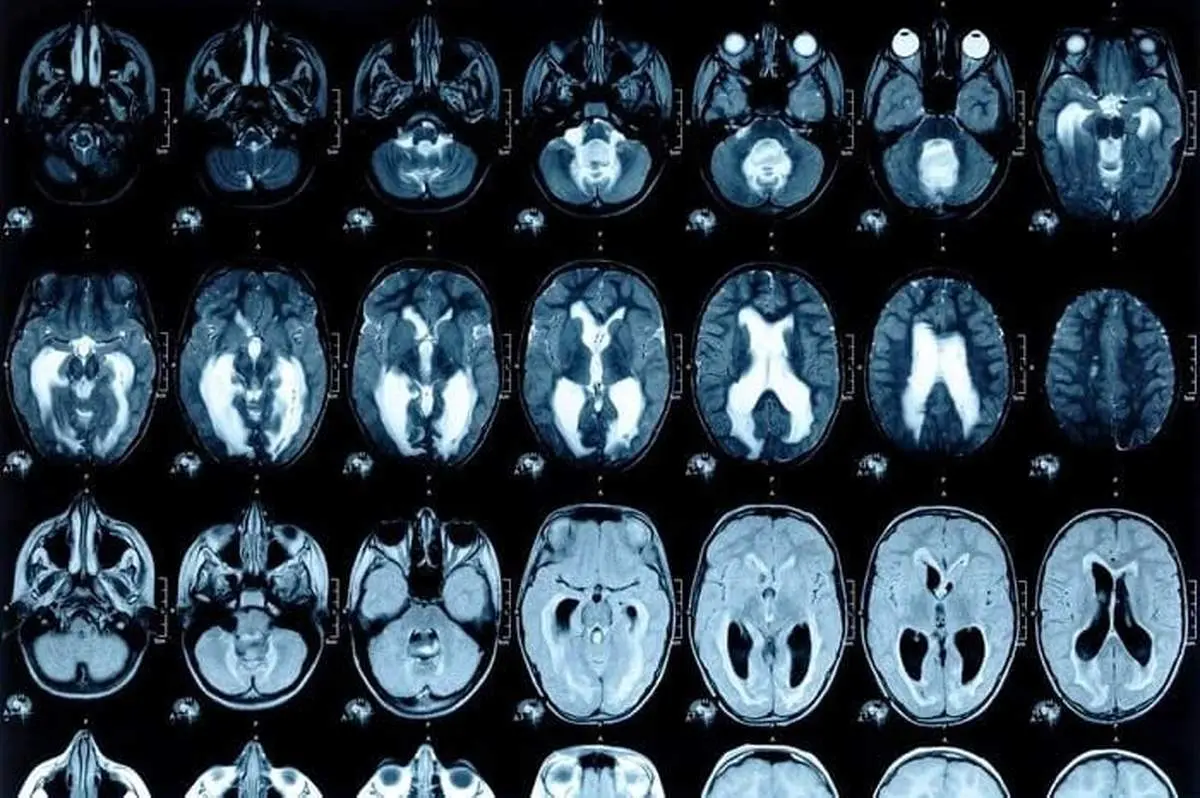

پزشکان پس از اسکن سر زن باردار این موضوع را به تایید رساند که در جمجمه اش میخی فرو رفته؛ سپس این خانم را در بیمارستان بستری کردند. زمانی که علت را از او پرسیدند، گفت که از دیگران شنیده بود که اگر این کار را انجام دهد، حتماً فرزند پسر به دنیا می آورد.